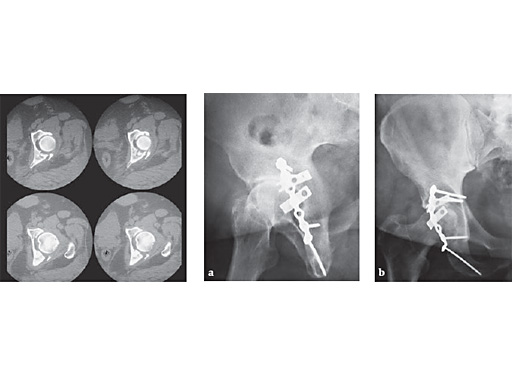

18-year-old male-missed injury

Case provided by Keith Mayo, Tacoma

The superior plate is a modified one-third tubular plate and represents the forerunner of the production plate which is seen inferiorly. Joint space narrowing likely represents combined pre surgical cartilage loss and secondary subsidence of elevated and grafted areas of marginal impaction.